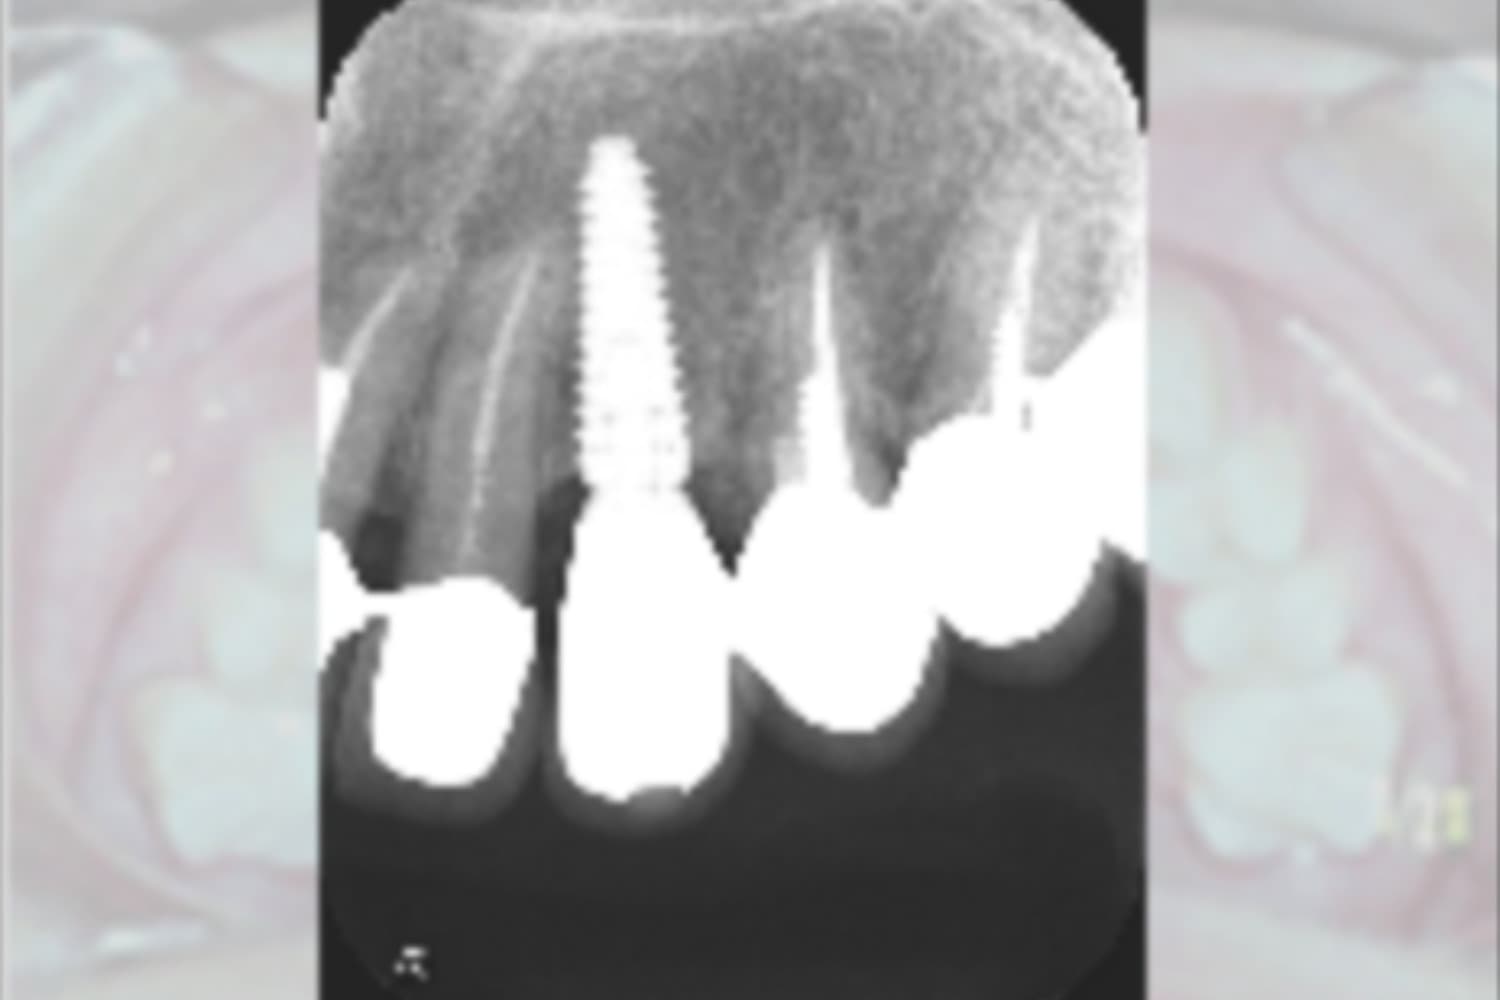

インプラントの症例

右上欠損部のインプラント治療

右上欠損部にインプラント治療を行なった

右上歯牙欠損部にインプラント治療希望

4カ月

10回

434,500円

・感染やインプラントの結合不良の可能性がある